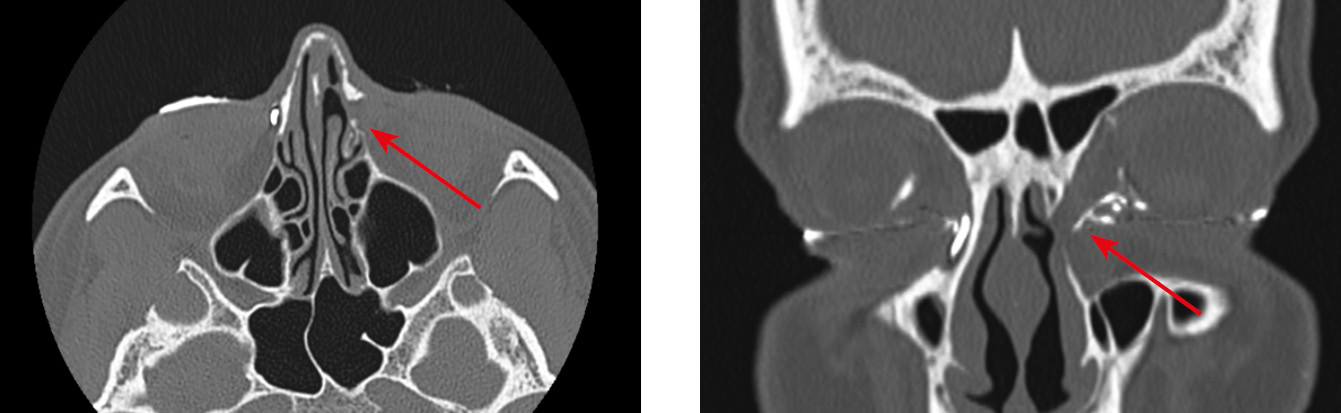

Наиболее распространенной причиной дакриоцистита оказалась ретроградная резекция крючковидного отростка с помощью обратного выкусывателя или при использовании микродебридера в ходе эндоназальной риноантростомии (12 случаев, 31,58 %). Интересно, что повреждение чаще всего было локализовано в области задневерхних отделов НСК, а также в области шейки слезного мешка (рис. 4). Наши данные согласуются с данными литературных источников [1, 2, 4–6, 8, 13, 14, 17].

Рис. 4. Облитерация носослезного протока справа на уровне верхней трети после осуществления ретроградной инфундибулотомии справа. Мультиспиральная компьютерная томография выполнена через 3 мес. после проведенной FESS (стрелки)

Fig. 4. Right nasolacrimal duct obliteration at the level of the upper third after right retrograde infundibulotomy. Multislice computed tomography at 3 months after FESS (arrows)